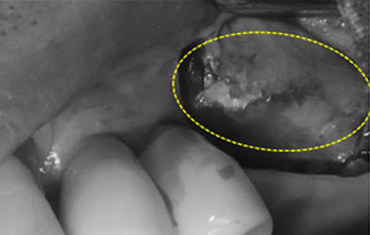

타 치과의 뼈 이식 후 골조직

램브란트치과 상인점 뼈이식 후 골조직